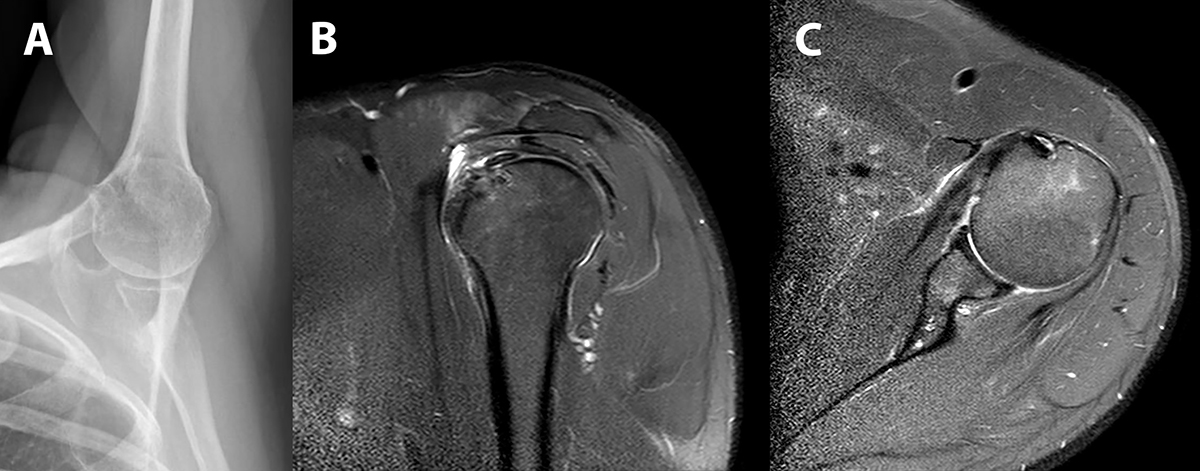

El paciente se colocó en posición de silla de playa luego de un bloqueo regional. Se realizó una artroscopia diagnóstica por un portal posterior estándar. Luego de descartar patologías asociadas intraarticulares o en el espacio subacromial, se realizaron 2 portales accesorios uno anterolateral y uno anterior (fig. 2). Luego la cámara se cambió hacia el portal anterolateral, y utilizamos el portal anterior para crear un espacio virtual entre el tendón conjunto y el subescapular con la radiofrecuencia. De esta manera encontramos la calcificación con facilidad y removimos la misma en forma completa. Una vez removido el depósito de calcio se realizó la reparación del defecto con un arpón biodegradable de 5.5 mm con doble sutura reforzada. El paciente utilizó un cabestrillo por 4 semanas. Los ejercicios de codo muñeca y mano se autorizaron desde el primer día postoperatorio, y a partir de la cuarta semana el paciente comenzó con rehabilitación. Luego de la sexta semana se autorizaron ejercicios de movilidad activa y a la octava semana se comenzó con un programa de fortalecimiento muscular progresivo. El paciente se encontraba sin dolor y con movilidad completa a los 3 meses de la cirugía. Los estudios postoperatorios a los 4 meses de la cirugía mostraban la ausencia de depósitos de calcio remanentes y la integridad del tendón reparado (fig. 3). El paciente retomó los entrenamientos de tenis al cuarto mes y la competencia a los 5 meses de la cirugía. En el último control al año de la cirugía el paciente continuaba asintomático y jugando al tenis al mismo nivel que antes de la lesión.

Figura 3: A) Radiografía de hombro izquierdo 1 semana luego de la cirugía que muestra la ausencia de calcio remanente. B y C) Cortes sagital y axial respectivamente de la resonancia nuclear magnética 3 meses luego de la cirugía demostrando la ausencia del depósito de calcio y la indemnidad del tendón reparado.

También es motivo de debate en la literatura si los defectos remanentes luego de la extracción del calcio deben ser reparados. Algunos investigadores no realizan en forma rutinaria la reparación de los defectos y confían en la capacidad auto-cicatrización del tendón.14 Sin embargo, Seil y cols.6 evaluaron una serie de pacientes tratados con la remoción de los depósitos de calcio sin reparación de los defectos remanentes y el 31% de los pacientes tenían un defecto en el tendón en los controles realizados con ecografía a los 24 meses del postoperatorio. Por otra parte, en un estudio reciente, Balke y cols.18 reevaluaron 48 pacientes que habían sido sometidos a la remoción artroscópica de las calcificaciones sin reparación de los tendones y evaluaron a los mismos con ecografía en el seguimiento. Once pacientes (23%) presentaban una lesión parcial del supraespinoso en el seguimiento. Nosotros preferimos reparar los defectos del tendón para facilitar el proceso de cicatrización. En nuestro paciente realizamos la reparación artroscópica del defecto remanente con un arpón de doble sutura al igual que lo realizamos cuando tratamos las calcificaciones del supraespinoso. En los controles postoperatorios se puede observar el tendón cicatrizado en la resonancia (fig. 3).